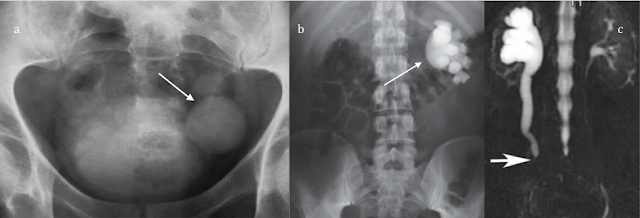

- Obstrucción de la vía urinaria: Existen múltiples causas de obstrucción de la vía urinaria, como por ejemplo, la hiperplasia benigna de la próstata, litiasis urinaria, un tumor que obstruya el lumen urinario? etc. Todas estas condiciones son capaces de producir estasis urinaria

- Sacos de orina sin drenaje: Fundamentalmente causados por divertículos; los cuales pueden verse en toda la vía urinaria, especialmente en la vejiga, el riñón y la uretra. Otras condiciones pueden ser las válvulas uretrales.

- Litiasis: La presencia de litiasis muchas veces favorece la persistencia de gérmenes en la vía urinaria, pues los antibióticos no son capaces de erradicarlas completamente de las mismas.